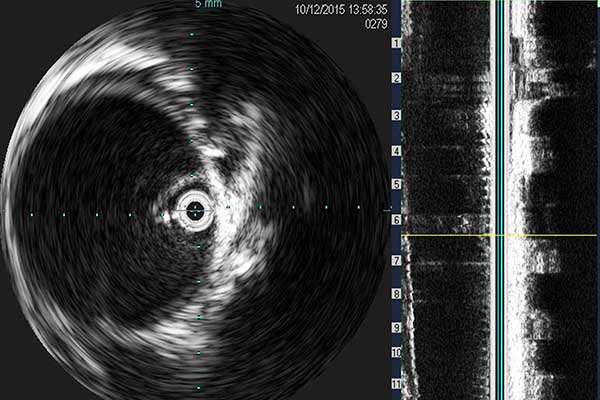

• IntraVascular UltraSound (IVUS)

• This procedure helps an interventional cardiologist with a closure look at the lesion and provides additional information before or after an intervention